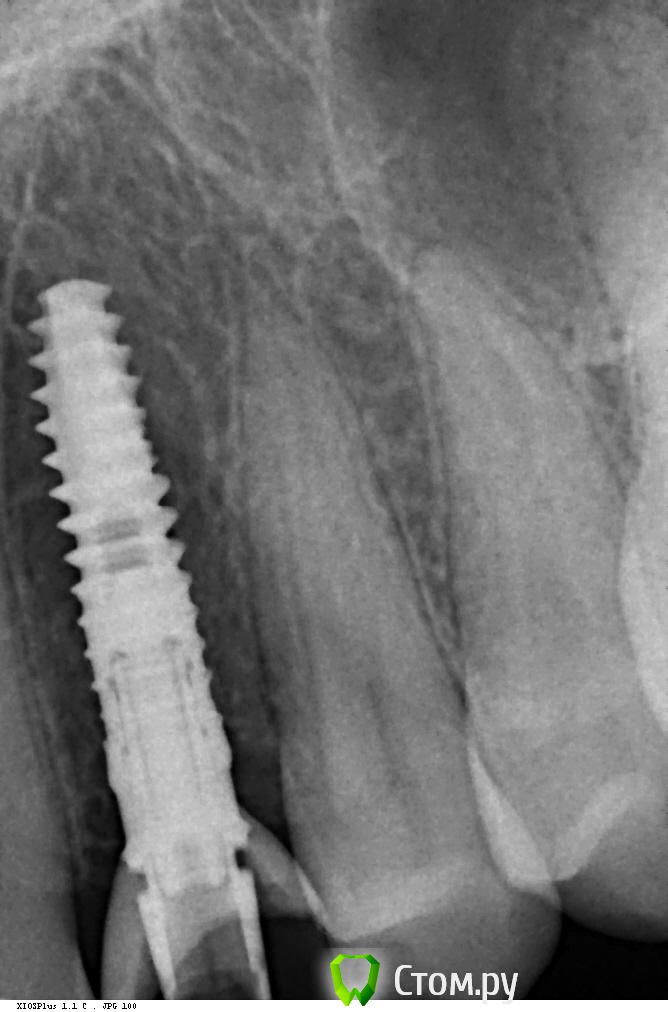

CSS Опубликовано 13 февраля, 2014 Поделиться Опубликовано 13 февраля, 2014 А как насчет снимка в студию??? 1 Ссылка на комментарий

bugroff87 Опубликовано 14 февраля, 2014 Автор Поделиться Опубликовано 14 февраля, 2014 Вот! Ссылка на комментарий

CSS Опубликовано 14 февраля, 2014 Поделиться Опубликовано 14 февраля, 2014 А как перкуссия? Ссылка на комментарий

CSS Опубликовано 14 февраля, 2014 Поделиться Опубликовано 14 февраля, 2014 В смысле ЗВУК? Ссылка на комментарий

bugroff87 Опубликовано 15 февраля, 2014 Автор Поделиться Опубликовано 15 февраля, 2014 Безболезненна, вообще ничего не беспокоит. Ссылка на комментарий

Чертков Александр Опубликовано 15 февраля, 2014 Поделиться Опубликовано 15 февраля, 2014 Вынимать. Ссылка на комментарий